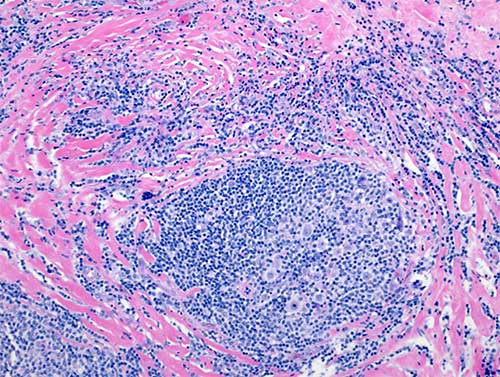

Hodgkin lymphoma biopsy

Hodgkin lymphoma biopsy demonstrating rare Hodgkin and Reed-Sternberg cells in a dense immune infiltrate. (Image courtesy of Dr. Giulino Roth)